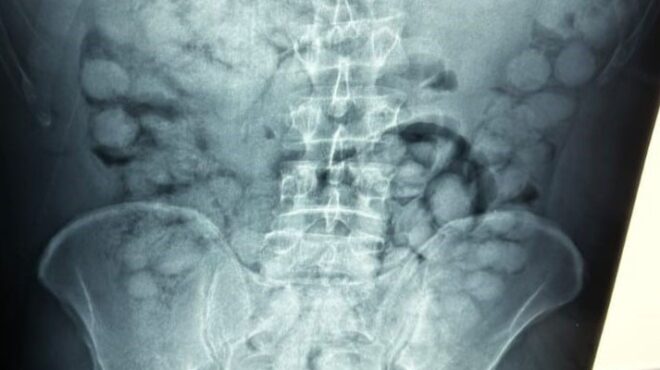

Ο άνδρας, που ταξίδευε από Βραζιλία μέσω Γαλλίας, είχε καταπιεί 100 συσκευασίες κοκαΐνης. Η κάθε συσκευασία ήταν 10 γραμμαρίων και καθαρότητας 90%.